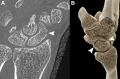

CT systems equipped with photon-counting detectors (PCDs), referred to as photon-counting CT (PCCT), are beginning to change imaging in several subspecialties, such as cardiac, vascular, thoracic, and musculoskeletal radiology. Evidence has been building in the literature underpinning the many advantages of PCCT for different clinical applications. These benefits derive from the distinct features of PCDs, which are made of semiconductor materials capable of converting photons directly into electric signal. PCCT advancements include, among the most important, improved spatial resolution, noise reduction, and spectral properties. PCCT spatial resolution on the order of 0.25 mm allows for the improved visualization of small structures (eg, small vessels, arterial walls, distal bronchi, and bone trabeculations) and their pathologies, as well as the identification of previously undetectable anomalies. In addition, blooming artifacts from calcifications, stents, and other dense structures are reduced. The benefits of the spectral capabilities of PCCT are broad and include reducing radiation and contrast material dose for patients. In addition, multiple types of information can be extracted from a single data set (ie, multiparametric imaging), including quantitative data often regarded as surrogates of functional information (eg, lung perfusion). PCCT also allows for a novel type of CT imaging, K-edge imaging. This technique, combined with new contrast materials specifically designed for this modality, opens the door to new applications for imaging in the future.